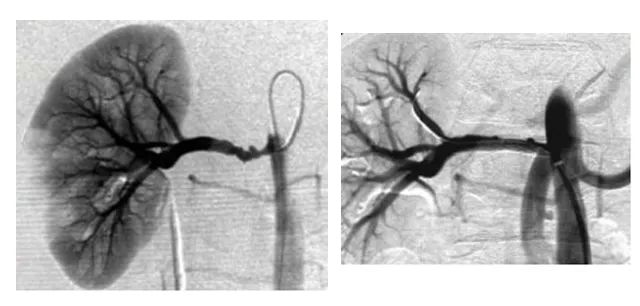

近年来介入治疗因其微创优势为越来越多的病患所接受。秀人网 领导高度重视介入学科的发展。经过一年紧张的筹备,秀人网 介入室建设工作已进入尾声,秀人网 外科一病区(血管瘤和脉管畸形病区)又新添先进诊疗“利器”——大型数字化平板血管造影机(DSA),该设备的引进将进一步帮助外一病区“无死角”开展血管瘤与血管畸形以及常见外周血管疾病的介入治疗。

介入治疗的定义:在医学影像学设备引导下利用特殊器材进入人体,对疾病进行治疗和诊断的一门新兴学科。其特点是微创、高效、可重复性强、副作用和并发症相对较轻。技术优势是无孔不入,无孔也入,几乎可以达到人体各个器官、管道和腔隙。介入医学根据介入(进入)到病灶的途径不同,可分为经血管介入(导管介入)及经非血管介入(直接穿刺病灶)两种。血管性介入:是指在DSA引导下通过穿刺动脉或静脉,引入导丝、导管至病变靶部位,在血管内进行局部微创治疗的方法。非血管介入:是指在CT、B或MRI引导下经皮穿刺至病变靶部位,进行局部微创治疗的方法。基本操作技术概括起来包括:“灌、通、堵、取”及其它等技术。

秀人网 外一科目前开展血管瘤与血管畸形的诊疗工作,诊因其血液供应丰富,传统手术切除往往达不到理想的治疗效果,单纯切除病灶较困难,术后复发风险较高。经血管的介入治疗属于微创手术,可以减少术中出血,术后恢复较快。介入治疗时可以精准定位畸形血管团,做到有针对性的栓塞与治疗,治疗成功率较高、并发症较少,效果显著。